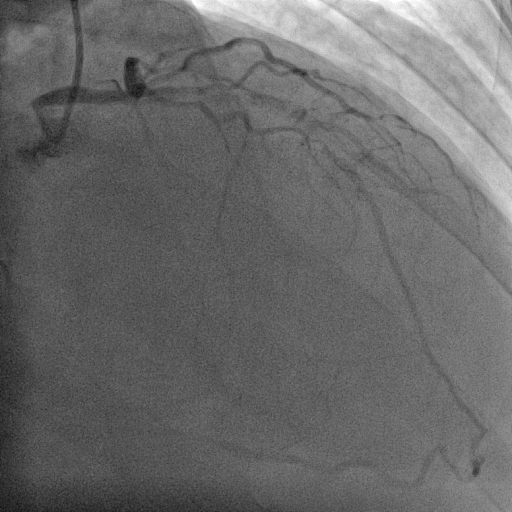

Coronary angiography was performed via right radial access with terumo radial TIG 5Fr catheter . Coronary artery angiogram revealed right dominance coronary artery system with RCA mid 100% with retrograde from LAD and LCx proximal 70%, distal 80% and LAD proximal 99% .

SHAHIDUL ISLAM_(S7_F1-50).avi

SHAHIDUL ISLAM_(S2_F1-57).avi

SHAHIDUL ISLAM_(S6_F1-102).avi